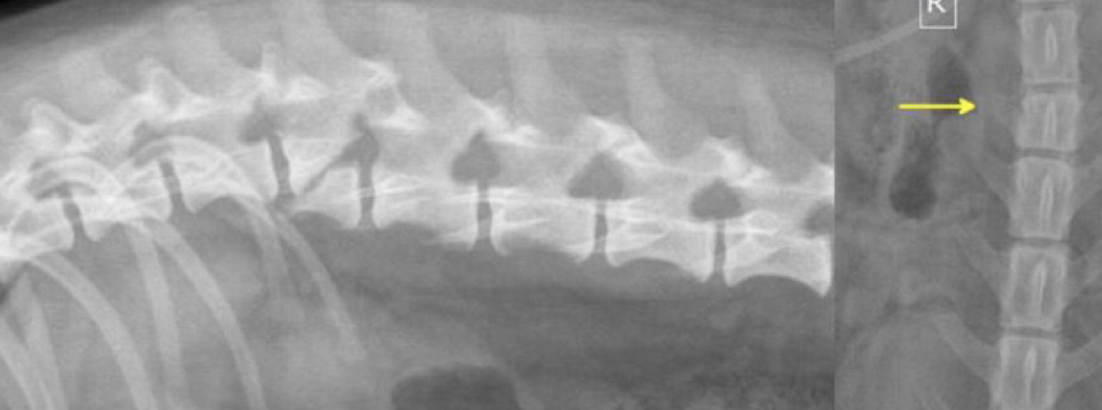

You have a dog that comes in with non-head involved ataxia. Both himdlimbs are involved and there is a lot of pain. You take rads and this is what you find. What is going on? How do you treat?

A

fracture

euthanasia, pain mgmt, stabilization, REFERRAL